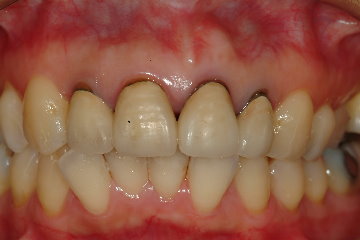

全瓷冠-上顎門牙根尖囊腫

審美牙科

全瓷冠